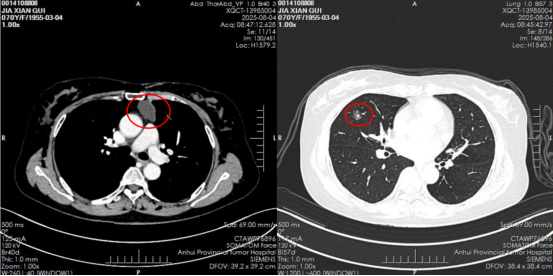

患者入住病房后,胸部肿瘤外科主任张安庆、主任医师张荣新和副主任医师周锐认真地阅读了患者的胸部增强CT,患者前纵隔肿物偏左侧,肺部病变位于右肺中叶,侧胸入路很难同时切除两处病变。剑突入路可以兼顾两侧胸腔和前部病变,而且国内外已有剑突入路进行肺癌根治术的报道。向患者及家属讲明情况,家属选择剑突入路进行微创手术治疗。